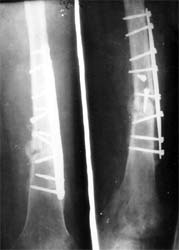

股骨远端骨折术后10年,4次手术均失败。经带锁髓内钉内 固定、植骨,骨生长因子和骨髓细胞注射,成功治愈